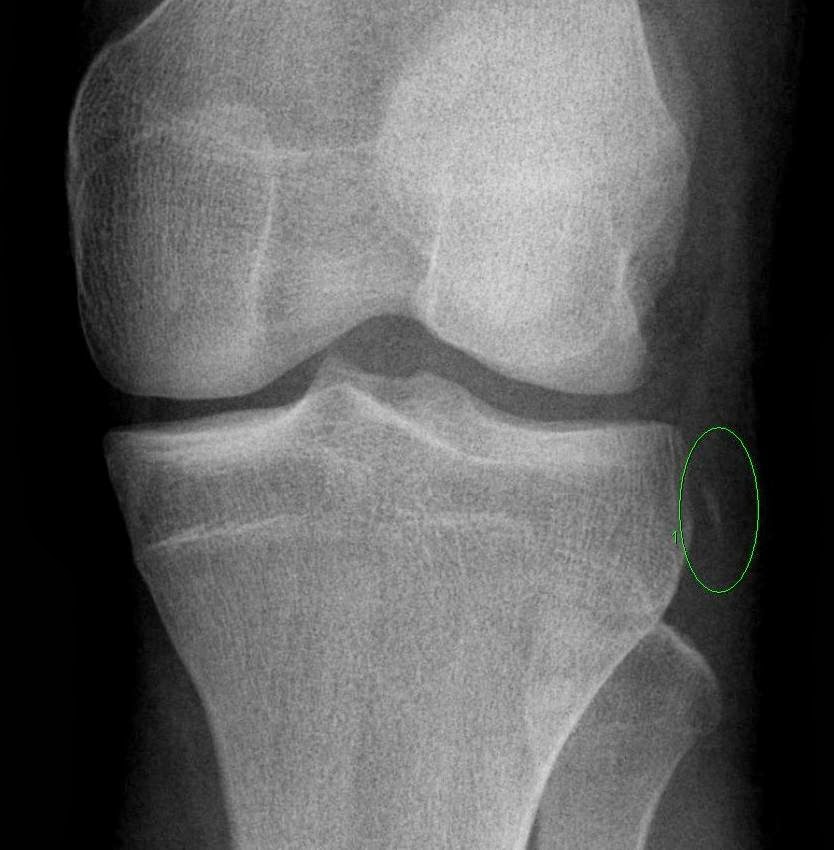

0 Segond fracture

Segond fracture = avulsion of the anterolateral aspect of the lateral tibial plateau

Mechanism - internal rotation of tibia + varus stress

Originally postulated - avulsion of the lateral capsular ligament,

Recent MR study suggests - it occurs at the distal attachments of the iliotibial tract or Lateral Collateral Ligament. (ref: CT and MRI of the Whole Body, Fifth Edition, John R. Haaga)

Most common ASSOCIATED injury - ACL tear (75-100%)

2nd MC - Meniscal tear (medial or lateral, mostly posterior horn)(66-75%).